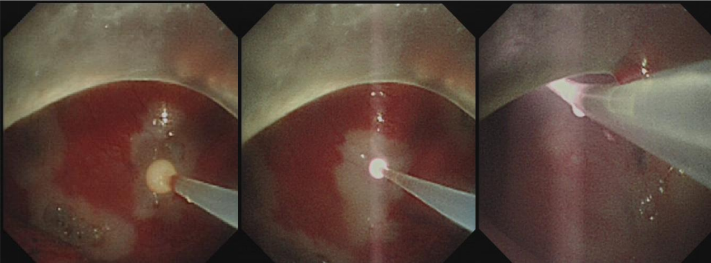

2.内科胸腔镜。主要用于胸膜病变的诊治。主要适应证:是不明原因胸腔积液诊断的“金标准”;需要在膈肌、纵隔和心包进行活检的病例等;恶性或良性顽固性胸腔积液的胸膜固定术;复发性气胸或慢性气胸的诊治;支气管胸膜瘘的治疗等。2018年中国医师协会“介入呼吸病 学工作委员会”举办了“介入呼吸 病学核心技术操作视频大赛”我院作品“内科胸腔镜常规检查教学视频 ”在比赛中荣获二等奖。

内科胸腔镜下治疗胸膜肿瘤